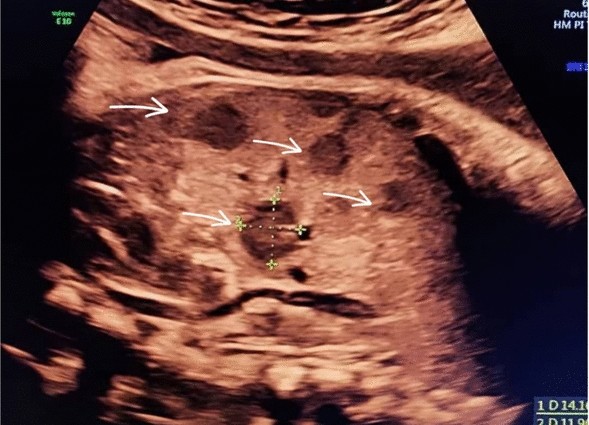

At 37 weeks of gestation, a routine third-trimester ultrasound revealed a hypoechoic lesions in the fetal liver. The lesions were well-circumscribed, measuring approximately 3.5 cm in diameter, and exhibited characteristics suggestive of a vascular tumor. Doppler imaging indicated hypervascularity, raising suspicion for a hemangioendothelioma. Furthermore, the fetal brain appeared normal upon prenatal evaluation. Amniotic fluid levels and fetal growth parameters were within normal limits, and no signs of fetal hydrops were observed. Amniotic fluid levels and fetal growth parameters were within normal limits, and no signs of fetal hydrops were observed. The fetal echocardiogram was normal. Figures 1, 2, and 3

Sagittal view of the fetal abdomen obtained with sonography, showing multiple hypoechoic lesions indicated by arrows